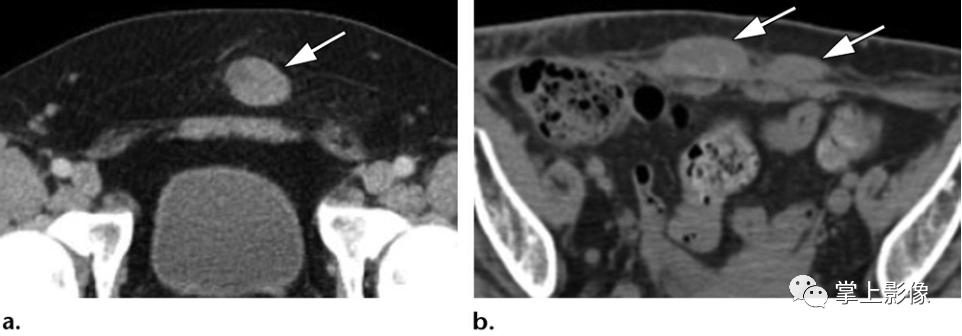

6例不同患者腹壁肉瘤的不同表现。比较可触及的腹壁肿块(a-c)和浅表溃疡性肿块(d-f)的表现。(A)一名38岁男性的轴位CT影像显示,皮下脂肪(经检查认为是腹股沟疝)有一边界清楚的小上皮样肉瘤(箭头)。(B)一名33岁男子的轴位CT影像显示,腹部下方肌肉深处平滑肌肉瘤(箭头)(病人右大腿亦有肿瘤[未显示])。(C)21岁男性轴位CT影像显示横纹肌肉瘤(箭头),患者的左大腿也有肿瘤(未显示)。(D)一名24岁男性的轴位CT影像显示一浅表性隆起性皮肤纤维肉瘤(箭头),影像上并无严重溃疡,但体格检查显示皮肤水肿及出血。(E)71岁女性的轴位CT影像显示浅表上皮样血管肉瘤(箭头),表现为溃疡性伤口。(F)一位62岁女性的轴位CT影像显示一深部浸润性滑膜肉瘤(箭头),表现为溃疡性伤口。所有诊断均经手术切除或活检证实